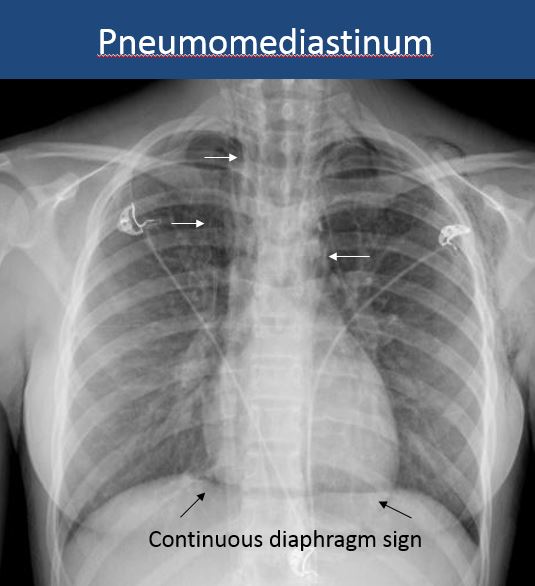

There is air in the soft tissues of the mediastinum. |

No | NA |

There is pneumopericardium. |